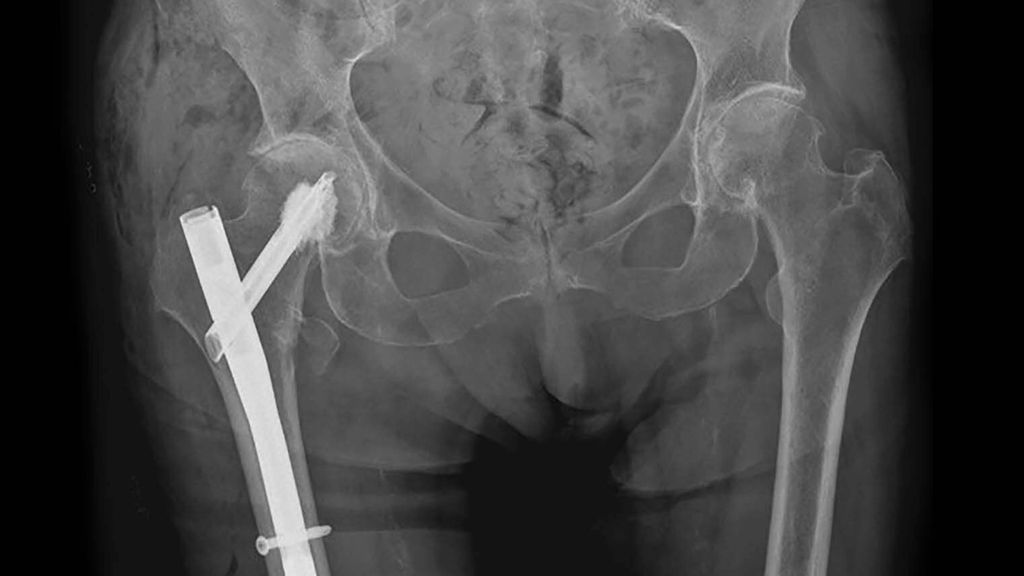

Pertrochantäre Femurfrakturen treten überwiegend bei älteren bzw. geriatrischen Patienten auf und sind daher mit hohen Mortalitäts- und Morbiditätsraten, schlechten funktionellen Ergebnissen und einer eingeschränkten Lebensqualität verbunden. Hierbei sind die Ursachen für eine proximale Femurfraktur bei älteren Menschen vielfältig. Neben einem erhöhten Sturzrisiko, zahlreichen internistischen (z.B. Diabetes mellitus, kardiovaskuläre Erkrankungen) und neurologischen Begleiterkrankungen (z.B. M. Parkinson, Polyneuropathie) sowie weiteren geriatrischen Syndromen wie beispielsweise die Sarkopenie, Mangelernährung oder eine Polypharmazie stellt insbesondere ein fortgeschrittenes Osteoporosestadium, einhergehend mit einer reduzierten Knochenqualität, die größte Herausforderung in der Frakturversorgung dar.2 Eine bewährte Methode zur Stabilisierung dieser Frakturen ist der Einsatz von intramedullären Nägeln, mit oder ohne die Verwendung von Knochenzement (Abb. 1).

Abb. 1: Röntgen Beckenübersicht: Z. n. zementaugmentierter Implantation eines intramedullären Nagels bei Z. n. pertrochantärer Femurfraktur rechts